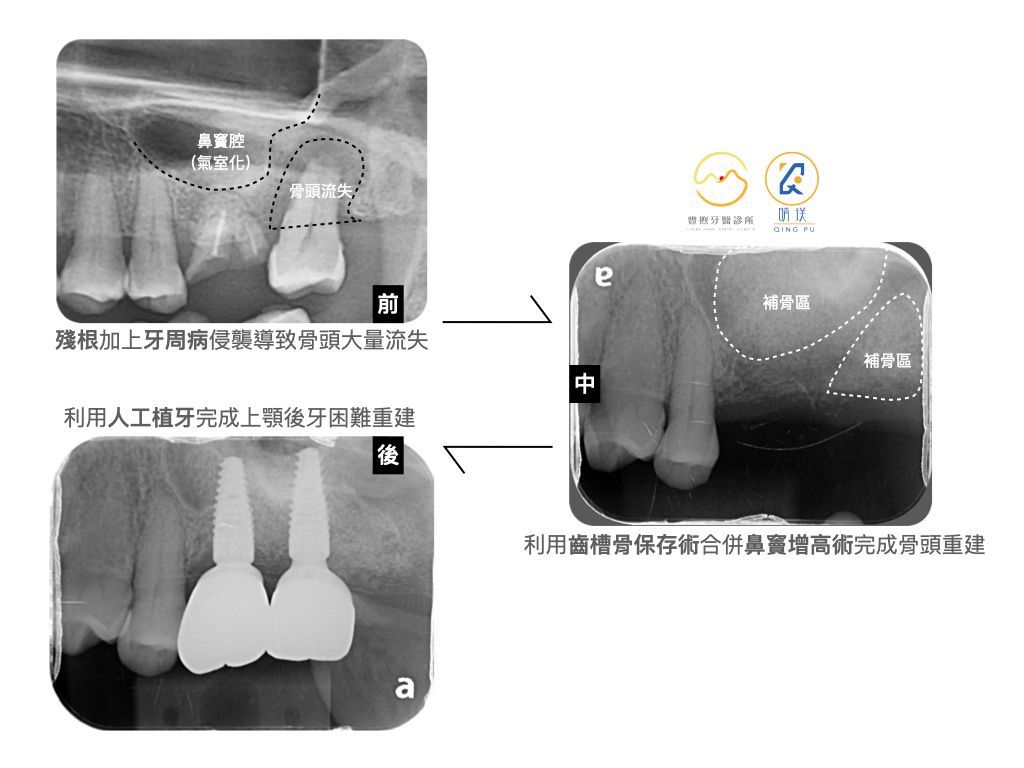

這位病人左上後牙第一大臼齒呈現殘根,上方鼻竇腔產生下移氣室化、第二大臼齒遭受牙周病侵襲導致骨頭大量流失,牙齒產生嚴重搖動。因此病人理解且接受拔牙。

審慎評估病人缺損的骨頭範圍,建議病人如果想以固定植牙假牙重建,那勢必得先把骨頭調整好,概念就像是蓋房子前我們先把土地整理好。

我們採取的手術是「齒槽骨保存術」以及「鼻竇增高術」

這裡所提的「齒槽骨保存術」就是在拔牙當下,我們會進行補骨,將缺損區域填復骨頭回去,然後等待傷口逐漸癒合。

而「鼻竇增高術」我們則是採取第二種術式:『側窗增高術』。理由是兩顆補骨範圍比較大,希望讓骨頭有良好的完整性。